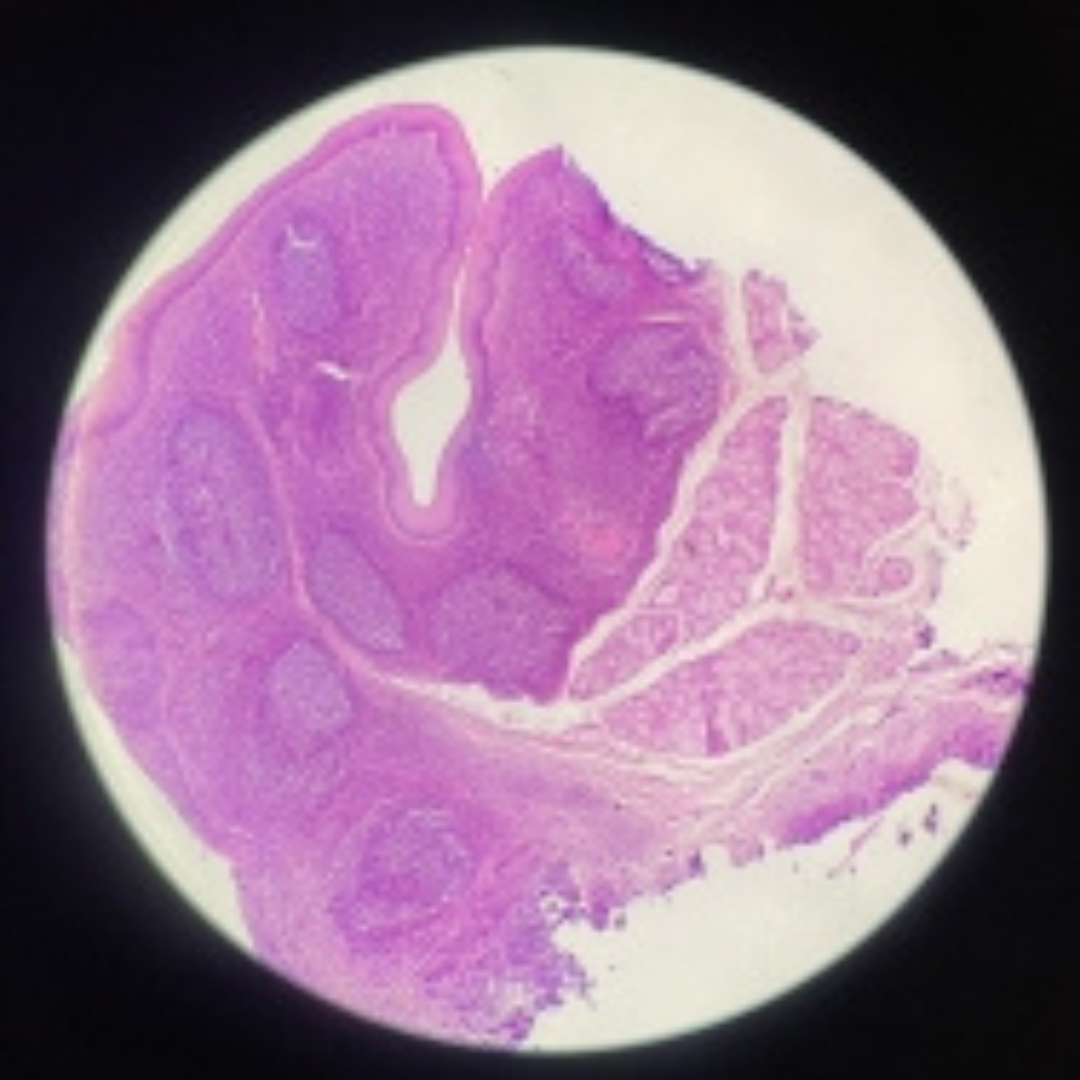

Tonsil

17

New cards

Tonsil

18

New cards

Tonsil

19

New cards

Tonsil